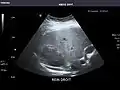

Kidneys: Right and left kidneys measure 11.5 cm and 12 cm in length respectively. No hydronephrosis. Small left lower pole kidney cyst.

Left kidney